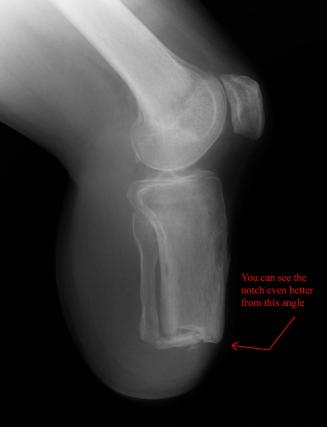

X-Rays Following Hyperextension of Left Ankle (January 31st 2006)

These x-rays were taken following a fluke event where Liam hyperextended his left ankle while playing an XBox 360 video game. As can be

seen in the images there are two (2) breaks that were produced from the hyperextension. One of the tibia bones has a hairline break and

the bone piece that spontaneously fused the tibia to the fibula has snapped. It took almost 2 weeks to determine that these breaks had

occurred. Due to Liam’s unique pain threshold and the lack of visible indicators, a break was not considered. Just another senseless

accident that resulted from the use of a violent video game. ;-) Yeah, right...